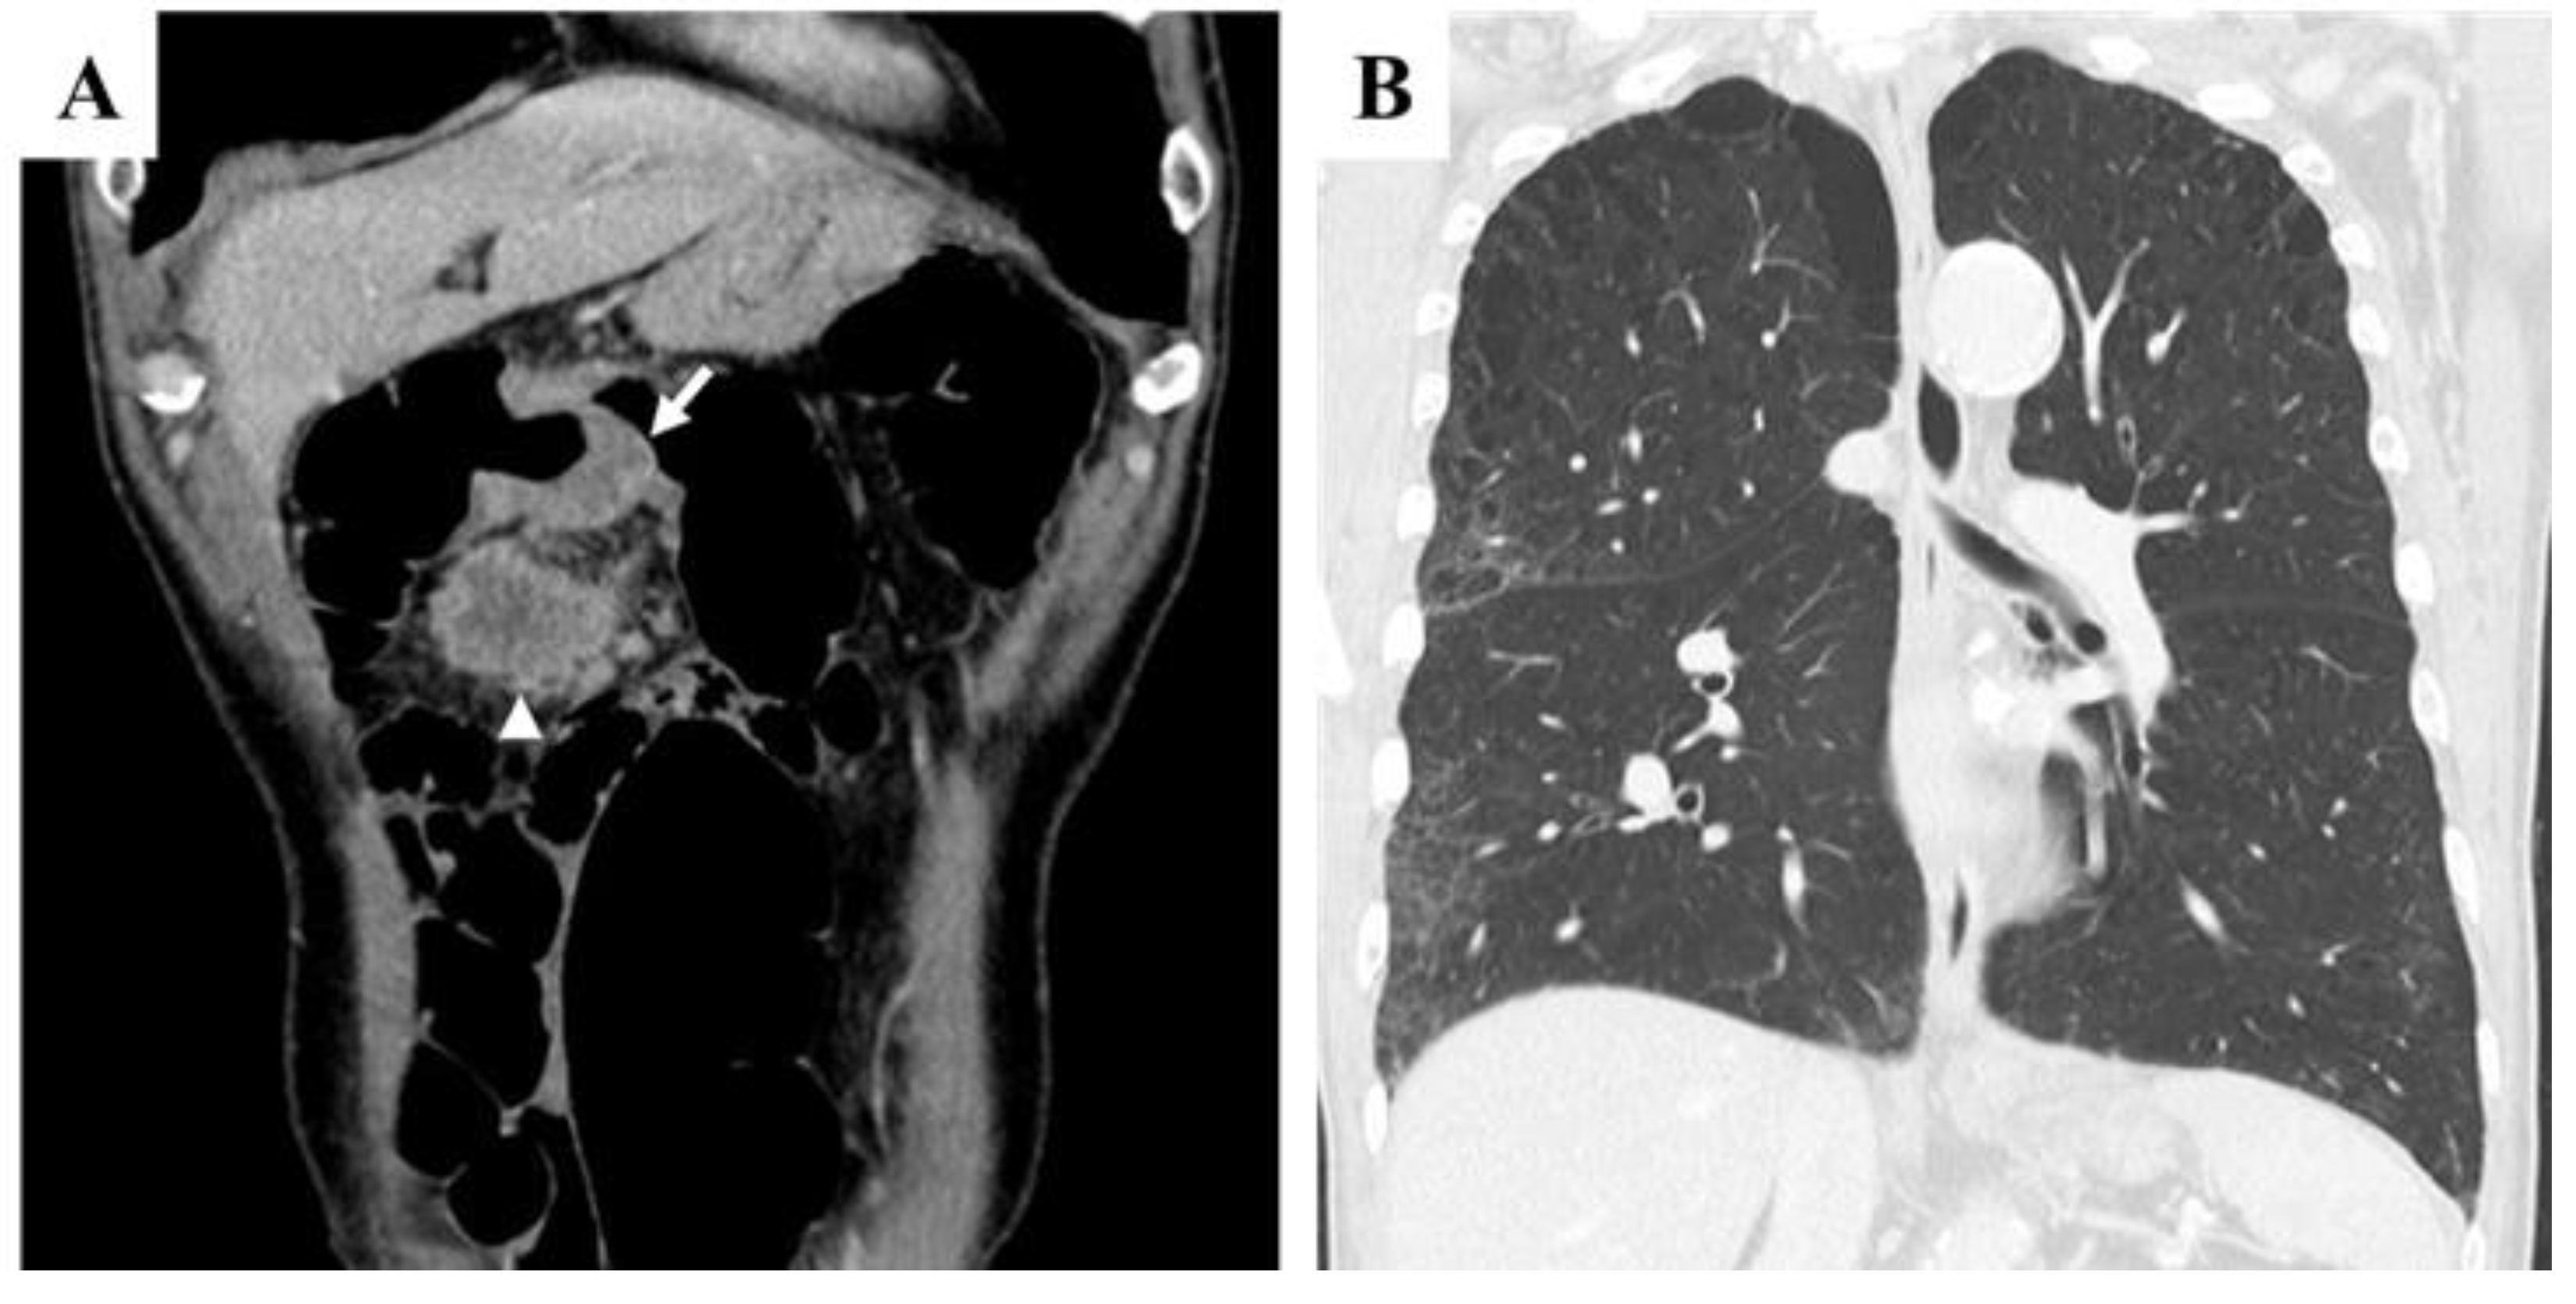

High-flow oxygen therapy was initiated; however, oxygen saturation remained precarious. The laboratory findings revealed worsening anemia, elevated liver enzymes, and significantly increased C-reactive protein (CRP) levels, suggesting a systemic inflammatory response. Chest CT imaging revealed marked progression of interstitial pneumonia in both lungs, which was most pronounced in the right lobe [Figure 3A]. Newly developed ground-glass opacities appeared in previously normal lung regions amid areas of emphysema. Additional findings included multiple infiltrative shadows, mild right lung volume reduction, and bilateral pleural effusion [Figure 3B]. These observations suggested worsening interstitial pneumonia with possible concomitant bacterial infection or drug-related lung toxicity. CT imaging of the chest and abdomen revealed no evidence of hematogenous metastasis, such as lung or liver involvement.

Figure 3. Chest CT findings at the time of transport due to acute respiratory failure. A and B: Marked deterioration of interstitial pneumonia was observed in both lobes, with the most pronounced changes in the right lobe. Ground-glass opacities appeared against a background of emphysematous lungs, accompanied by multiple infiltrative shadows, mild right lung volume reduction (A), and bilateral pleural effusion (B).